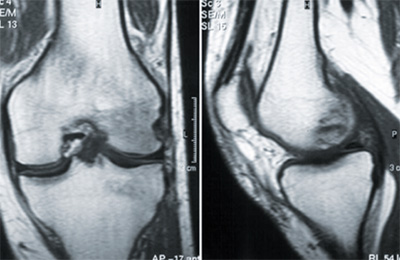

Enfin, dans une étude récente, l’oedème de la moelle osseuse a été montré comme le prédicteur indépendant le plus important de la progression radiographique des lésions. M. Ostergaard et coll. (3) ont présenté une mise à jour concernant l’utilisation d’un appareil IRM, l’E-MRI, IRM dédiée aux extrémités, moins coûteux que l’IRM classique et qui pourrait jouer un rôle important à l’avenir dans le diagnostic et le suivi de l’arthrite. Par exemple, un Esaote arthroscan E-MRI donne des informations similaires sur la synovite et les érosions à celles d’un IRM conventionnel du corps entier. Les images faites avec cet IRM s’améliorent d’année en année et permettent de penser que cet examen pourra être ajouté à l’examen clinique standard (figure).

Figure.

IRM genou gauche ; oedème de la moelle osseuse,

condyle externe du fémur.